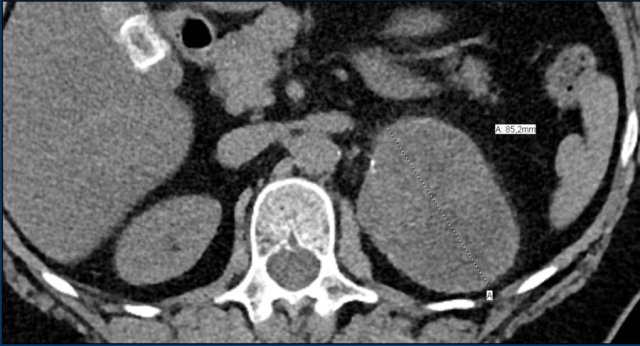

These images are of a 65- year-old female patient with an incidental discovery of a right adrenal mass on an abdominal ultrasound performed for renal stones.

The presence of microscopic fat is demonstrated by the signal drop on the opposed-phase image.

The patient was followed for 2 years, because the lesion is slightly inhomogeneous and measures 5.2 cm.

The lesion did not change in size and was not hormonally active.

It was diagnosed as a lipid-poor adenoma.